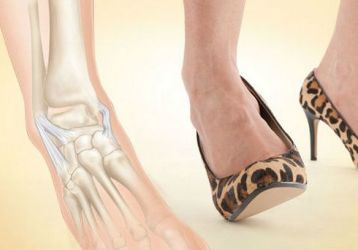

Болит косточка на ноге около большого пальца: лечение, причины и симптомы заболевания, как лечить недуг

Причины и симптомы появления косточки на большом пальце ноги. Развитие болезни, как лечить косточку у большого пальца на ноге: различные методы лечения.